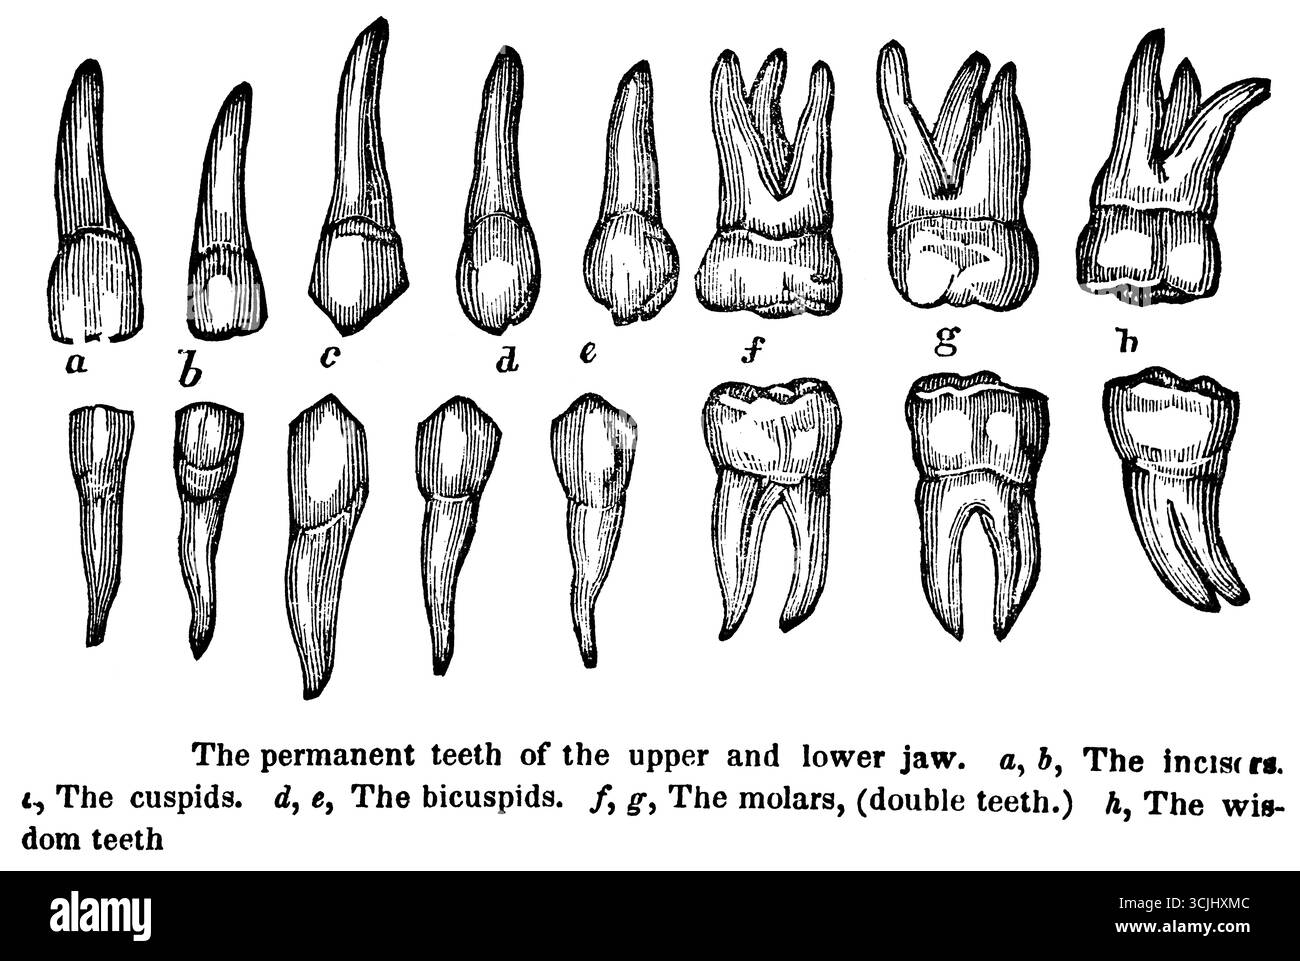

Anatomie des dents, dents permanentes de la mâchoire supérieure et inférieure, illustration historique 1858 Banque D'Imageshttps://www.alamyimages.fr/image-license-details/?v=1https://www.alamyimages.fr/anatomie-des-dents-dents-permanentes-de-la-machoire-superieure-et-inferieure-illustration-historique-1858-image699872668.html

Anatomie des dents, dents permanentes de la mâchoire supérieure et inférieure, illustration historique 1858 Banque D'Imageshttps://www.alamyimages.fr/image-license-details/?v=1https://www.alamyimages.fr/anatomie-des-dents-dents-permanentes-de-la-machoire-superieure-et-inferieure-illustration-historique-1858-image699872668.htmlRM3CJHXMC–Anatomie des dents, dents permanentes de la mâchoire supérieure et inférieure, illustration historique 1858

Anatomie des dents, corps de la mâchoire inférieure, illustration historique 1858 Banque D'Imageshttps://www.alamyimages.fr/image-license-details/?v=1https://www.alamyimages.fr/anatomie-des-dents-corps-de-la-machoire-inferieure-illustration-historique-1858-image699872662.html

Anatomie des dents, corps de la mâchoire inférieure, illustration historique 1858 Banque D'Imageshttps://www.alamyimages.fr/image-license-details/?v=1https://www.alamyimages.fr/anatomie-des-dents-corps-de-la-machoire-inferieure-illustration-historique-1858-image699872662.htmlRM3CJHXM6–Anatomie des dents, corps de la mâchoire inférieure, illustration historique 1858